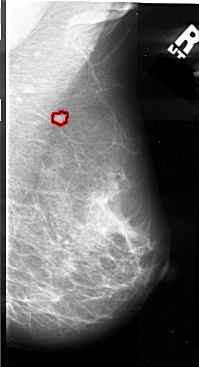

A_1061_1.LEFT_MLO

FILE: A_1061_1.LEFT_MLO.OVERLAY

TOTAL_ABNORMALITIES 1

ABNORMALITY 1

LESION_TYPE MASS SHAPE IRREGULAR MARGINS ILL_DEFINED

ASSESSMENT 4

SUBTLETY 2

PATHOLOGY MALIGNANT

TOTAL_OUTLINES 1

BOUNDARY